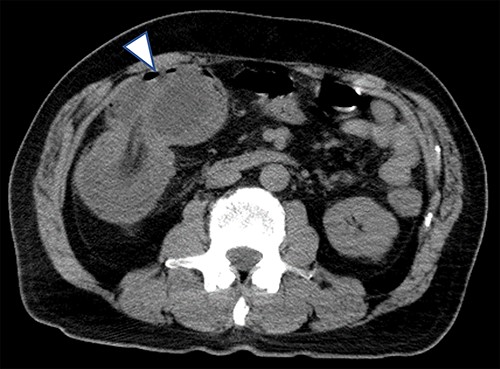

A 63-year-old male who had fever and dyspnea visited a medical institution. Both antigen and polymerase chain reaction (PCR) tests for SARS-CoV-2 were positive and he was hospitalized for treatment. Nine days after admission, he was transferred to our hospital due to deteriorating respiratory condition. After admission to our hospital, ventilator management and steroid administration were performed. After 3 days, his respiratory condition improved and he was able to withdraw from the ventilator. Computed tomography (CT) taken for observation of lung disease coincidentally showed cystic lesions in the right abdomen (Fig. 1). He had no abdominal symptoms at this time. The patient was discharged on the 18th day of hospitalization. He had diarrhea from the 15th day after discharge and abdominal pain from the next day. He consulted his family doctor on the 17th day because the abdominal pain persisted. CT examination revealed enlargement of cystic lesion and intussusception of the right colon (Fig. 2). The patient was transferred to our hospital as an emergency case. Physical findings showed fever with a body temperature of 38°C and tenderness in the right lower abdomen. Blood test showed an inflammatory reaction with a white blood cell count of 13 000/μl and C-reactive protein of 2 mg/dl. The SARS-CoV-2 PCR testing was negative. We performed emergency surgery on the same day.

Plain CT on the 13th day after COVID-19 onset (the day after withdrawal from the ventilator); a cystic lesion was found in the right lower abdomen (arrowhead).